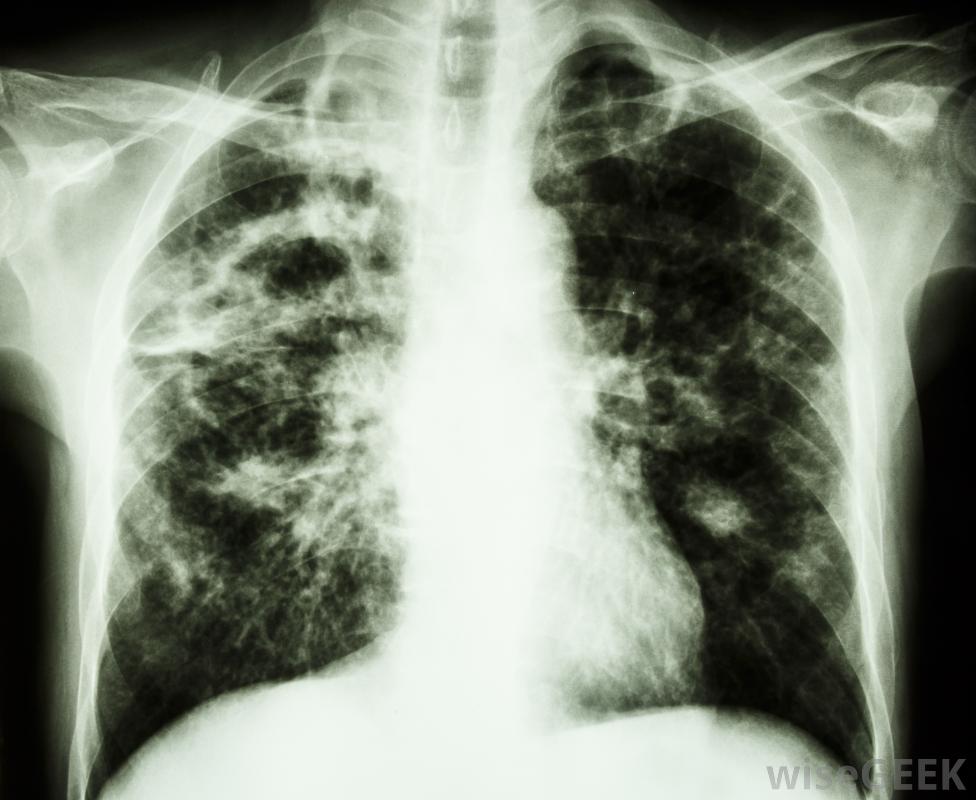

結核病通常影響肺部并引起盜汗和發燒。

一種臭名昭著的需氧菌是結核分枝桿菌,肺結核引起肺結核的有機體。肺結核是一種或多種結核分枝桿菌被吸入并在宿主體內成功繁殖,特別是在肺部。由于結核桿菌是有氧的,嗜氧的,免疫系統有限的個體的肺是一個好客的棲息地,大多數健康人都有免疫系統,可以防止這些需氧菌在體內停留并引起感染

肺結核是一種需氧菌,往往在肺部富氧的環境中茁壯成長。